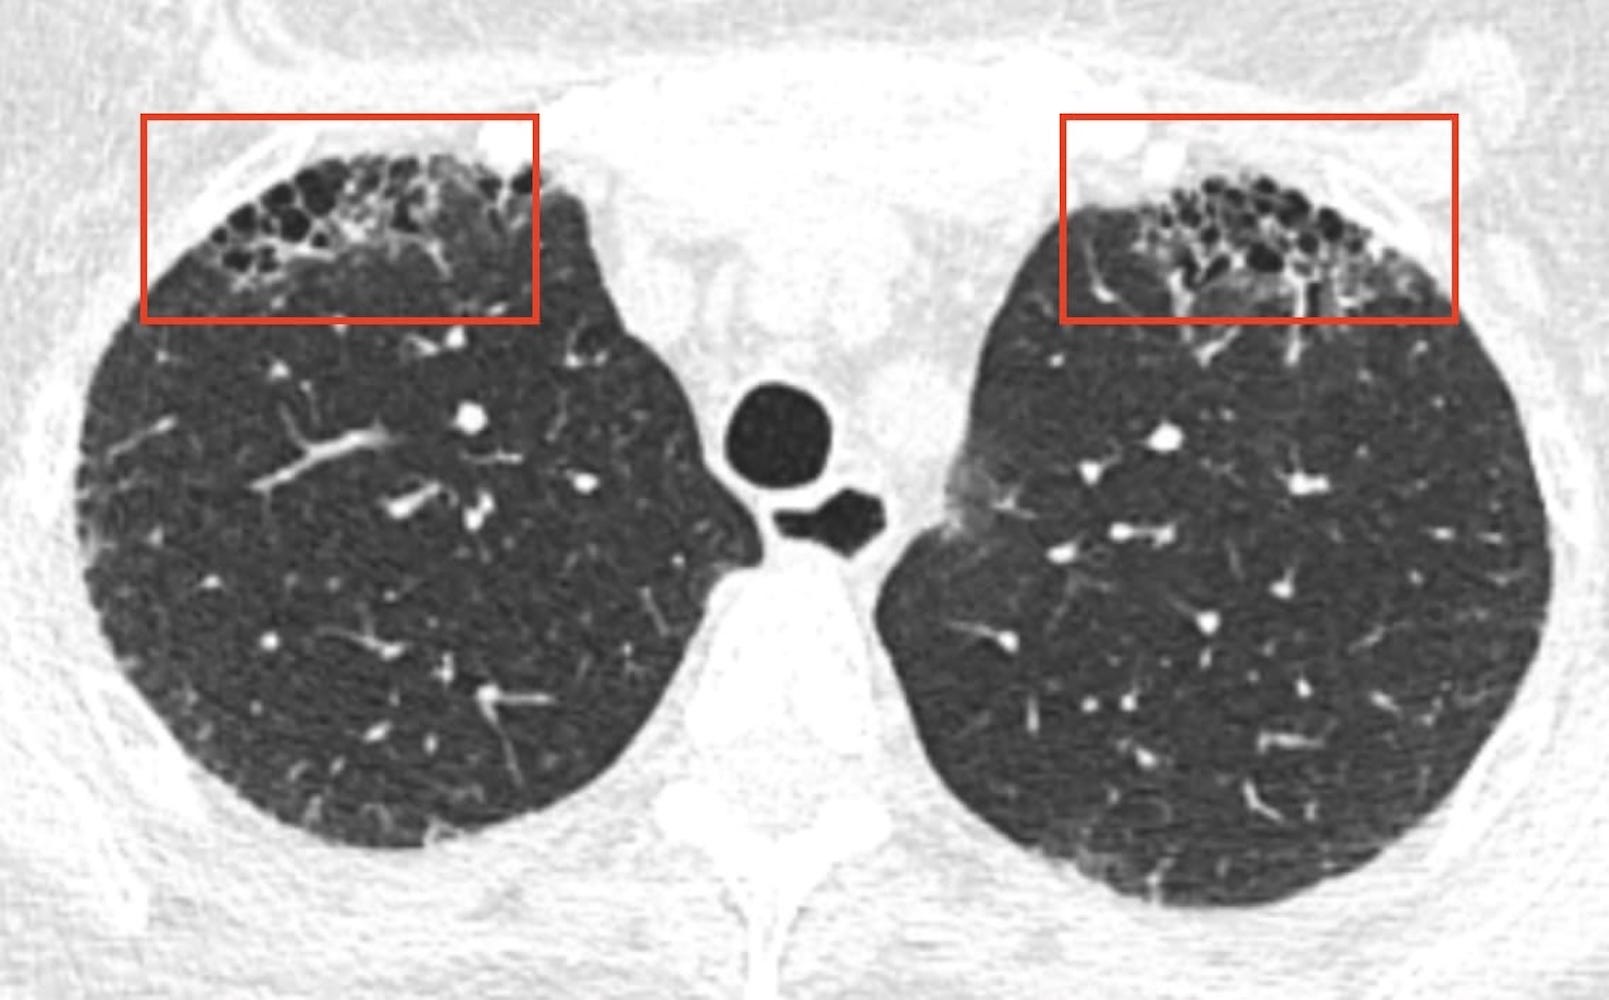

- Pleuropulmonary Fibroelastosis